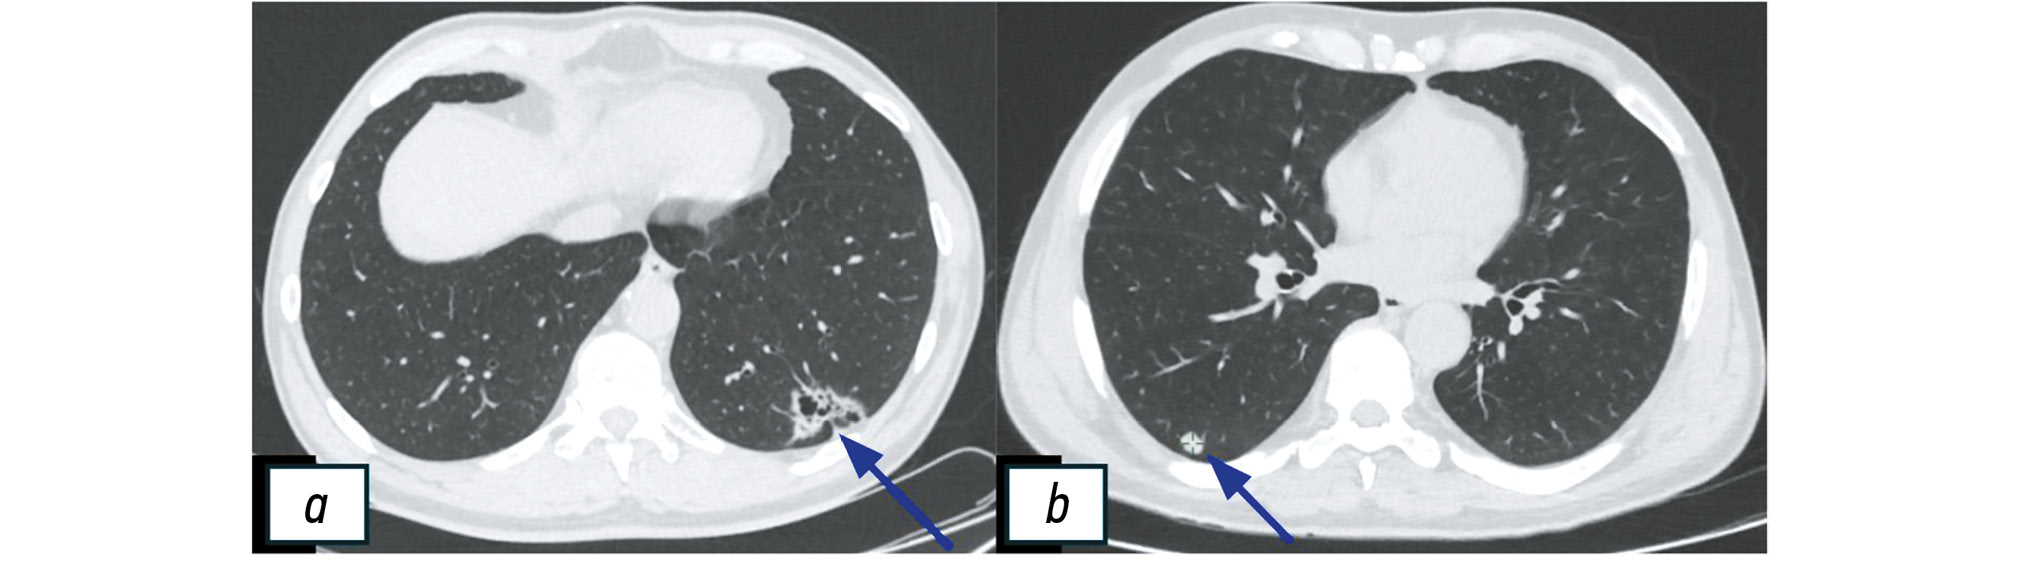

– A total of 78 patients were examined, and the diagnosis was histologically verified: two patients exhibited stage Ia and Ib lung cancer (Fig. 5), while 76 patients experienced other pulmonary diseases (Table 1).

Fig. 5. Chest computed tomography findings in patients with confirmed lung cancer (blue arrows). a, cystic and solid mass in the left lung (stage Ia); b, solid mass in the right lung (stage Ib).